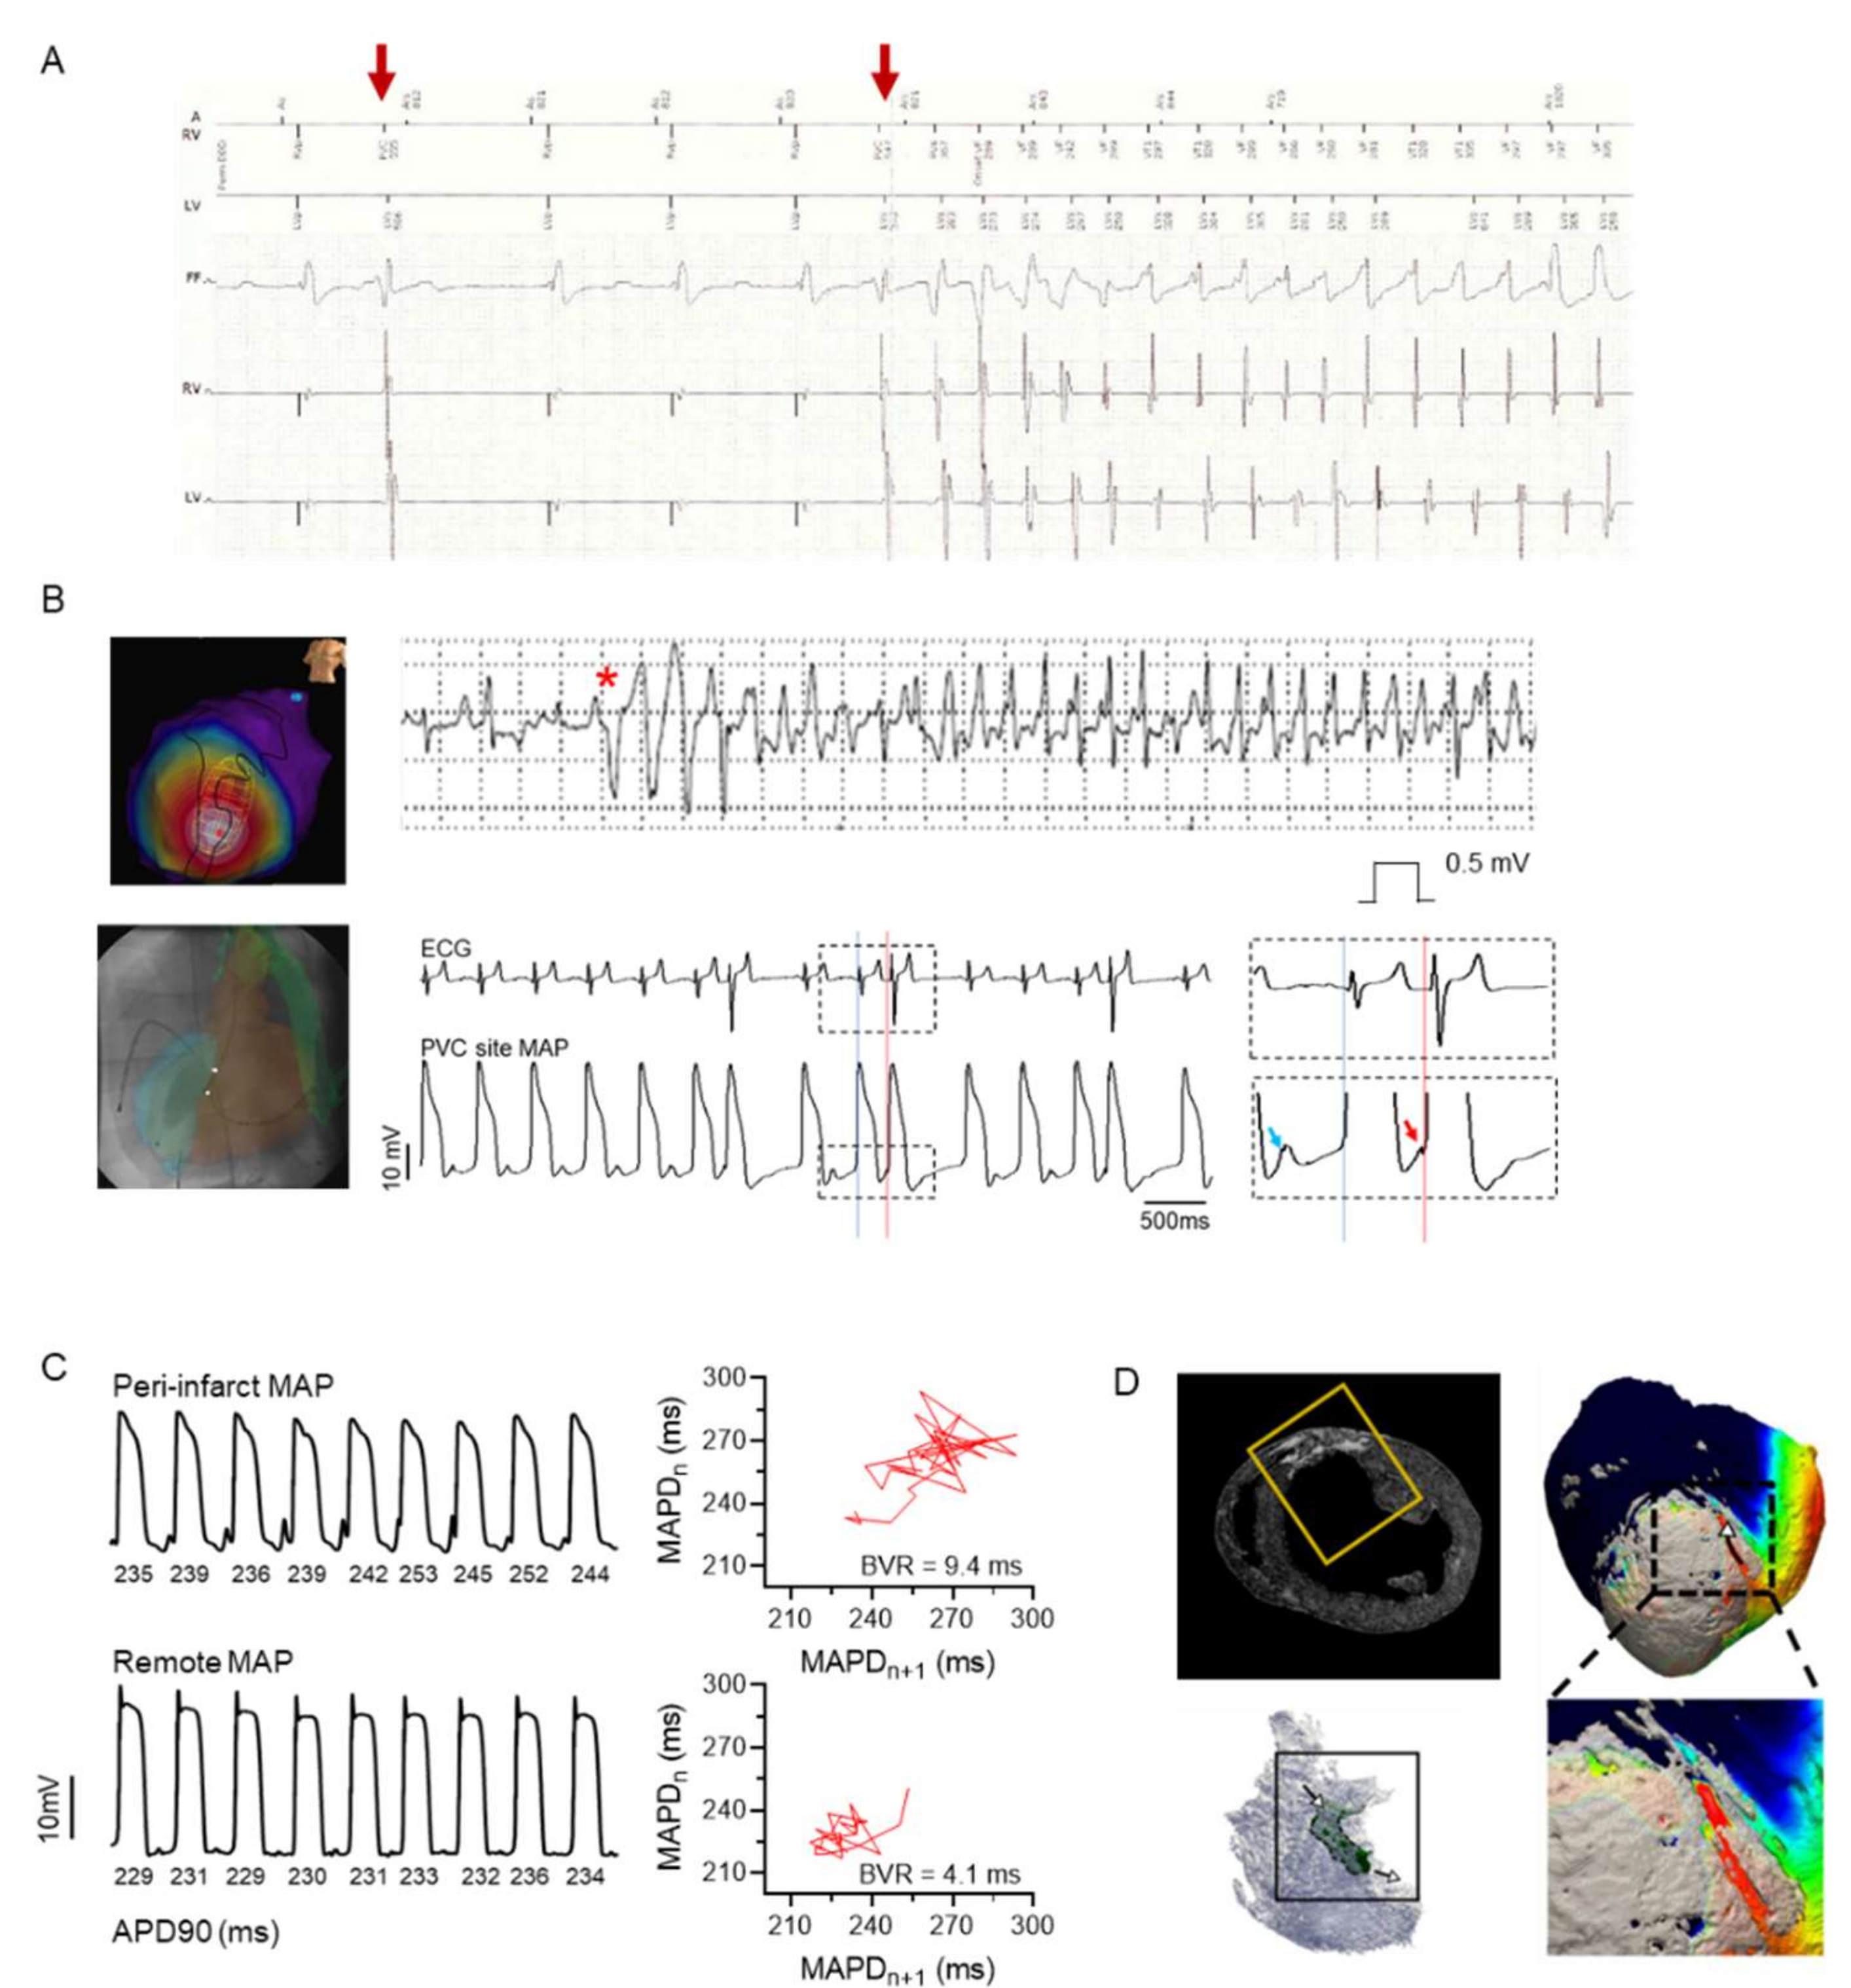

- Amoni, M.; Claus, P.; Dries, E.; Nagaraju, C.; De Buck, S.; Vandenberk, B.; Ingelaere, S.; Vermoortele, D.; Roderick, H.L.; Sipido, K.R.; et al. Discrete sites of frequent premature ventricular complexes cluster within the infarct border zone and coincide with high frequency of delayed afterdepolarizations under adrenergic stimulation. Heart Rhythm. 2021, 7, 67. [Google Scholar] [CrossRef]

- Dries, E.; Amoni, M.; Vandenberk, B.; Johnson, D.M.; Gilbert, G.; Nagaraju, C.K.; Puertas, R.D.; Abdesselem, M.; Santiago, D.J.; Roderick, H.L.; et al. Altered adrenergic response in myocytes bordering a chronic myocardial infarction underlies in vivo triggered activity and repolarization instability. J. Physiol. 2020, 598, 2875–2895. [Google Scholar] [CrossRef] [PubMed]